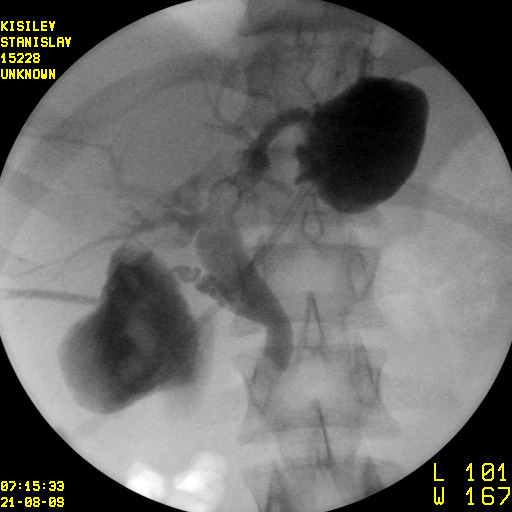

Минимально инвазивное лечение при эхинококковых кистах печени, осложнившихся прорывом в желчные протоки

Представлены клинические наблюдения редкого осложнения эхинококкоза печени – прорыва эхинококковой кисты в желчные протоки. Осложнение стало причиной обструкции желчных протоков, механической желтухи и холангита. Освещены этапы диагностики, роль УЗИ в выявлении осложнений эхинококкоза печени, рассмотрены способы минимально инвазивного лечения с применением эндоскопических и чрескожных технологий под контролем лучевых методов.